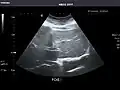

Spleen -